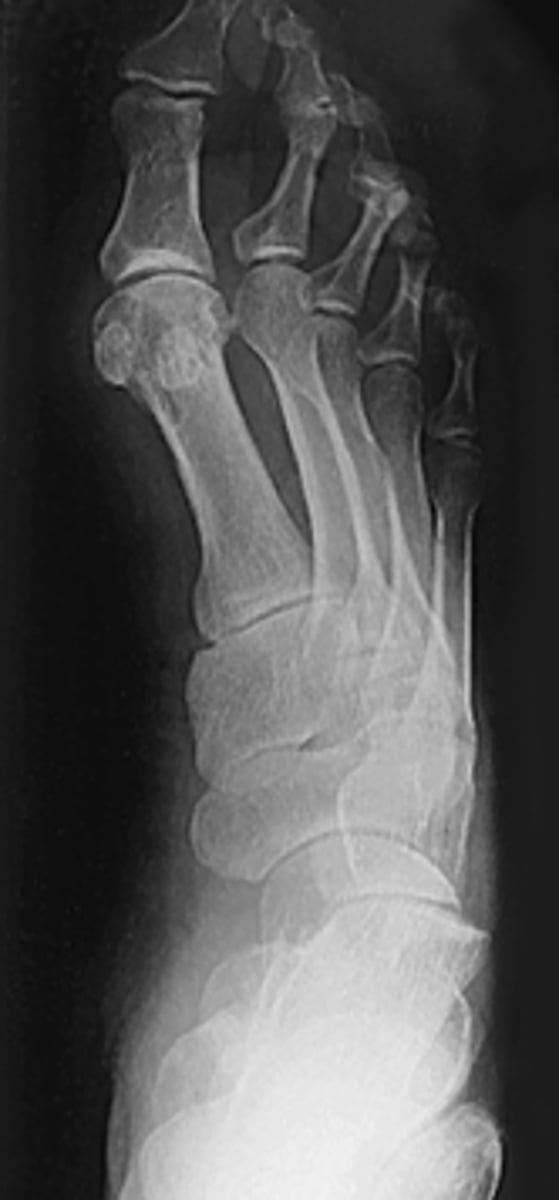

AP Weight Bearing Foot

What projection is this?

Evaluation Criteria for AP Weight Bearing Foot

- CR 15 posterior

- CR to base of MTs

- Bilateral feet demonstated

- Phalanges and MTs not rotated